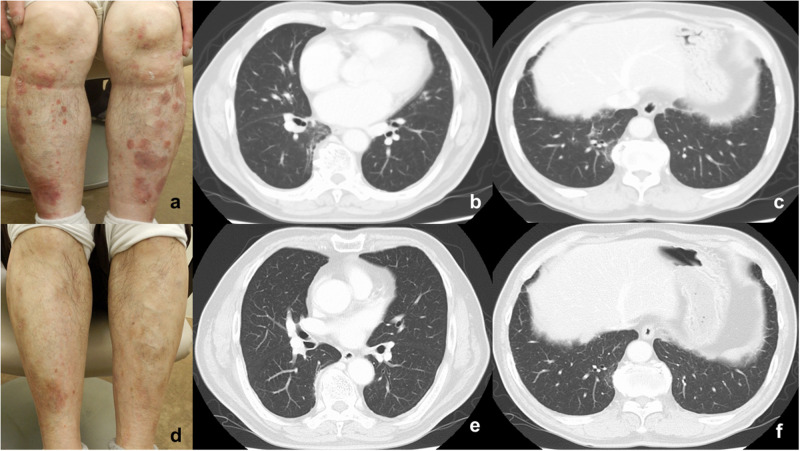

本病例报告描述了一名银屑病合并间质性肺炎(IP)的患者,其表现为线状混浊,接受了deucravacitinib治疗,旨在强调deucravacitinib在改善IP方面的潜在作用。银屑病是一种慢性免疫介导的皮肤疾病,涉及辅助性T (Th) 17细胞,常伴有全身合并症。Deucravacitinib是一种选择性口服酪氨酸激酶2 (TYK2)抑制剂,靶向白介素(IL)-23和I型干扰素,在银屑病治疗中显示出很强的疗效和安全性。间质性肺炎(IP)是一组以炎症、纤维化和进行性呼吸衰退为特征的肺部疾病。细胞因子在其发病机制中起关键作用。新的证据表明,银屑病具有更高的IP风险,可能是由于共享IL-23/IL-17途径。患者在deucravacitinib治疗后,皮肤和肺部表现明显改善,KL-6水平也有明显改善。TYK2介导与IP相关的关键促纤维化和促炎症细胞因子的下游信号传导。因此,我们认为deucravacitinib可能通过阻断这些信号通路来促进IP的改善,从而抑制慢性T细胞驱动的炎症和纤维化。进一步积累病例和持续的研究对于推进TYK2抑制剂在知识产权管理中的临床应用的讨论至关重要。

This case report describes a patient with psoriasis and interstitial pneumonia (IP) presenting with linear opacities who was treated with deucravacitinib, aiming to highlight the potential role of deucravacitinib in improving IP. Psoriasis is a chronic immune-mediated skin disease involving T helper (Th) 17 cells, often accompanied by systemic comorbidities. Deucravacitinib, a selective oral tyrosine kinase 2 (TYK2) inhibitor targeting interleukin (IL)-23 and type I interferons, has shown strong efficacy and safety in psoriasis treatment. Interstitial pneumonia (IP) is a group of lung diseases characterized by inflammation, fibrosis, and progressive respiratory decline. Cytokines play key roles in its pathogenesis. Emerging evidence suggests that psoriasis has higher risks of IP, possibly due to shared IL-23/IL-17 pathway. The patient showed marked improvement in skin and lung findings, along with KL-6 levels after deucravacitinib treatment. TYK2 mediates downstream signaling of key pro-fibrotic and pro-inflammatory cytokines involved in IP. Therefore, we consider that deucravacitinib may have contributed to the improvement of IP by blocking these signaling pathways, thereby suppressing chronic T cell-driven inflammation and fibrosis. Further accumulation of cases and continued research will be essential in advancing discussions on the clinical utility of TYK2 inhibitors in IP management.